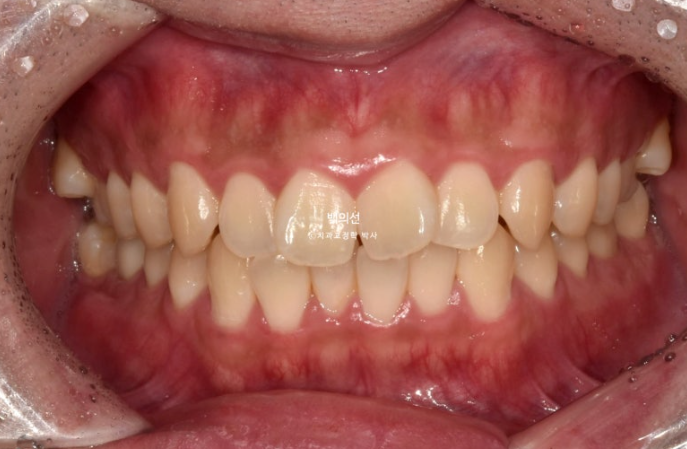

25.05

중심선은 잘 맞고

교합은 좋습니다.